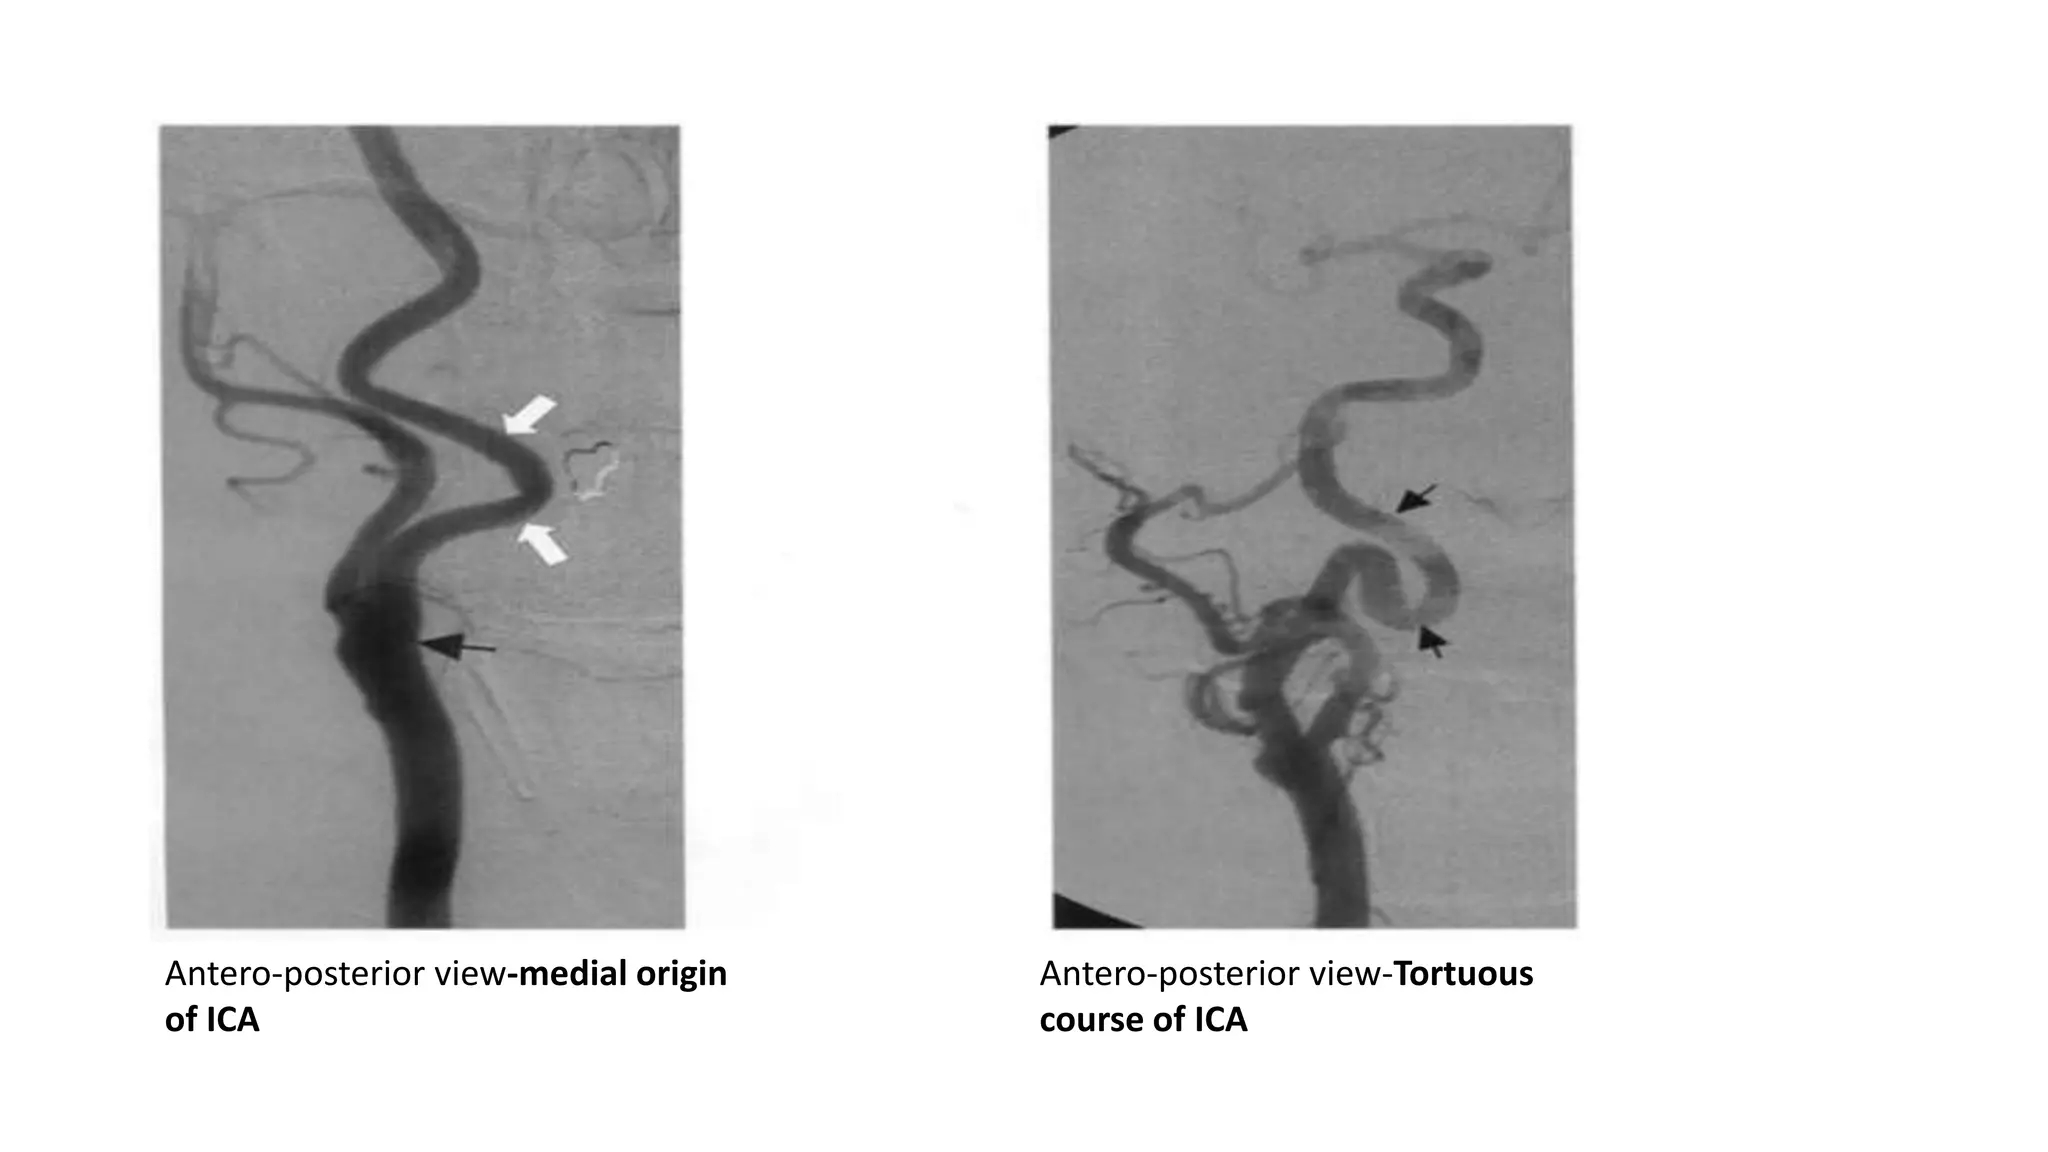

Cervical segment(C1)

Normal variants:

1)High bifurcation(up to C1)

or

low bifurcation(up to T2)

2)Medial origin-

• 10% pts

• can present as retropharyngeal

pulsatile mass

3)Tortuous course

Low bifurcation at C7 level-oblique anteroposterior angio

ICA

Antero-posterior view-medial origin

of ICA

Antero-posterior view-Tortuous

course of ICA